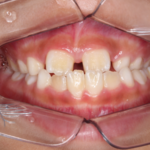

治療途中の矯正の症例

Before After 治療途中の小児矯正の症例です。あごの成長を利用しながら ...